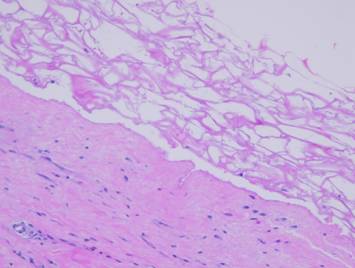

Once the wound is epithelialized and closed, there is no longer any inflammation or wound repair stimulus, so the proliferative phase ceases.  However, the strata of the wound continue their programmed sequences until they reach a state of stability or completion.  There are three notable events in the process of wound and scar maturation.  The first is the completion of the repair process leading to consolidation of the fibrosis.

Left upper, two panes showing a young scar at the time of complete epithelialization, and then how it evolves into a more contracted and stronger cicatrix.  Right, the sequence of fibroplasia and its consolidation as already explained on the preceding panels.  Top, the appearance of histio-fibroblasts, with early collagen deposition.  Second, an increase in cell and collagen density, with early lamellation and orientation of the cells and scar bundles.  Third, cell and collagen packing are denser, interlaced with mature vessels.  Bottom, new scar is at its densest, made from thick, non-compliant, highly stratified collagen-fibroblast bundles.  This is the peak of the acute scar, having been generated in a time frame of 2 to 4 weeks after initial injury.  If there is no further inflammation or other stimulus to wound module proliferation (which will continue to make new young scar), this peak proliferative scar will start to modify back toward something resembling normal dermis or muscular fascias, a process that will take weeks or months to complete.  Left lower, a point of interest.  In the other images right, the view is orthogonal to the wound surface revealing a cross section of layered scar.  The fibrocytes appear flattened and spindle shaped.  However, in this view, a tangential section parallel to the surface through the mid zone of the healing wound, it can be seen that the fibrous cells are actually flattened and wide.  They are compressed and spread by the tensions and geometries within the developing fibrous mesh of collagen and connective proteins.